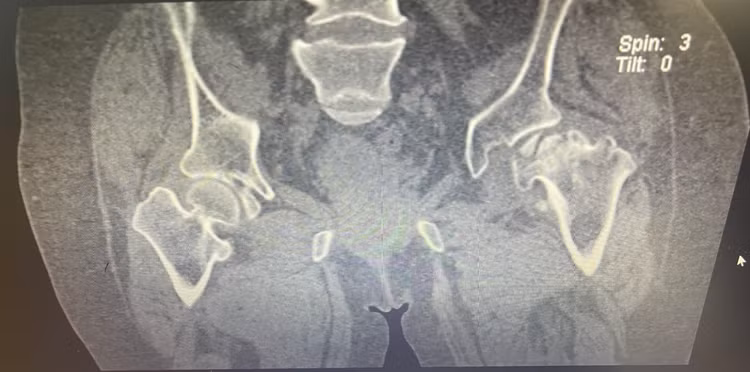

| Hình ảnh chụp cận lâm sàng X-quang trước và sau trước phẫu thuật của người bệnh P.T.C |

Kết quả thăm khám cận lâm sàng cho thấy người bệnh bị hoại tử chỏm xương đùi trái. Sau khi được hội chẩn về trường hợp ca bệnh đặc biệt, người bệnh P.T.C đã được chỉ định phẫu thuật bóc tách, cắt cổ xương đùi, tạo hình ổ cối, doa ống tuỷ và lựa chọn khớp phù hợp với thể trạng người bệnh.

Hình ảnh chụp CT trước phẫu thuật của người bệnh P.T.C |

Đây là trường hợp thay khớp háng nhân tạo cực kỳ đặc biệt. Bệnh nhân bị ảnh hưởng chất độc màu da cam, rối loạn phát triển hệ vận động dẫn đến toàn bộ vùng ổ cối xương chậu không phát triển, đường kính nhỏ hơn so với người phát triển bình thường. Đặc biệt, chiều dài xương đùi, chỏm xương đùi và đường kính xương đùi của người bệnh rất ngắn.

Trong khi đó, bộ phẫu thuật thay khớp chỉ được dùng cho người trưởng thành. Với tình trạng người bệnh có nhiều thay đổi về giải phẫu như trên đã đặt ra những khó khăn, đòi hỏi bác sĩ phẫu thuật phải có trình độ chuyên môn cao và phải chuẩn bị nhiều phương án trước khi tiến hành phẫu thuật.